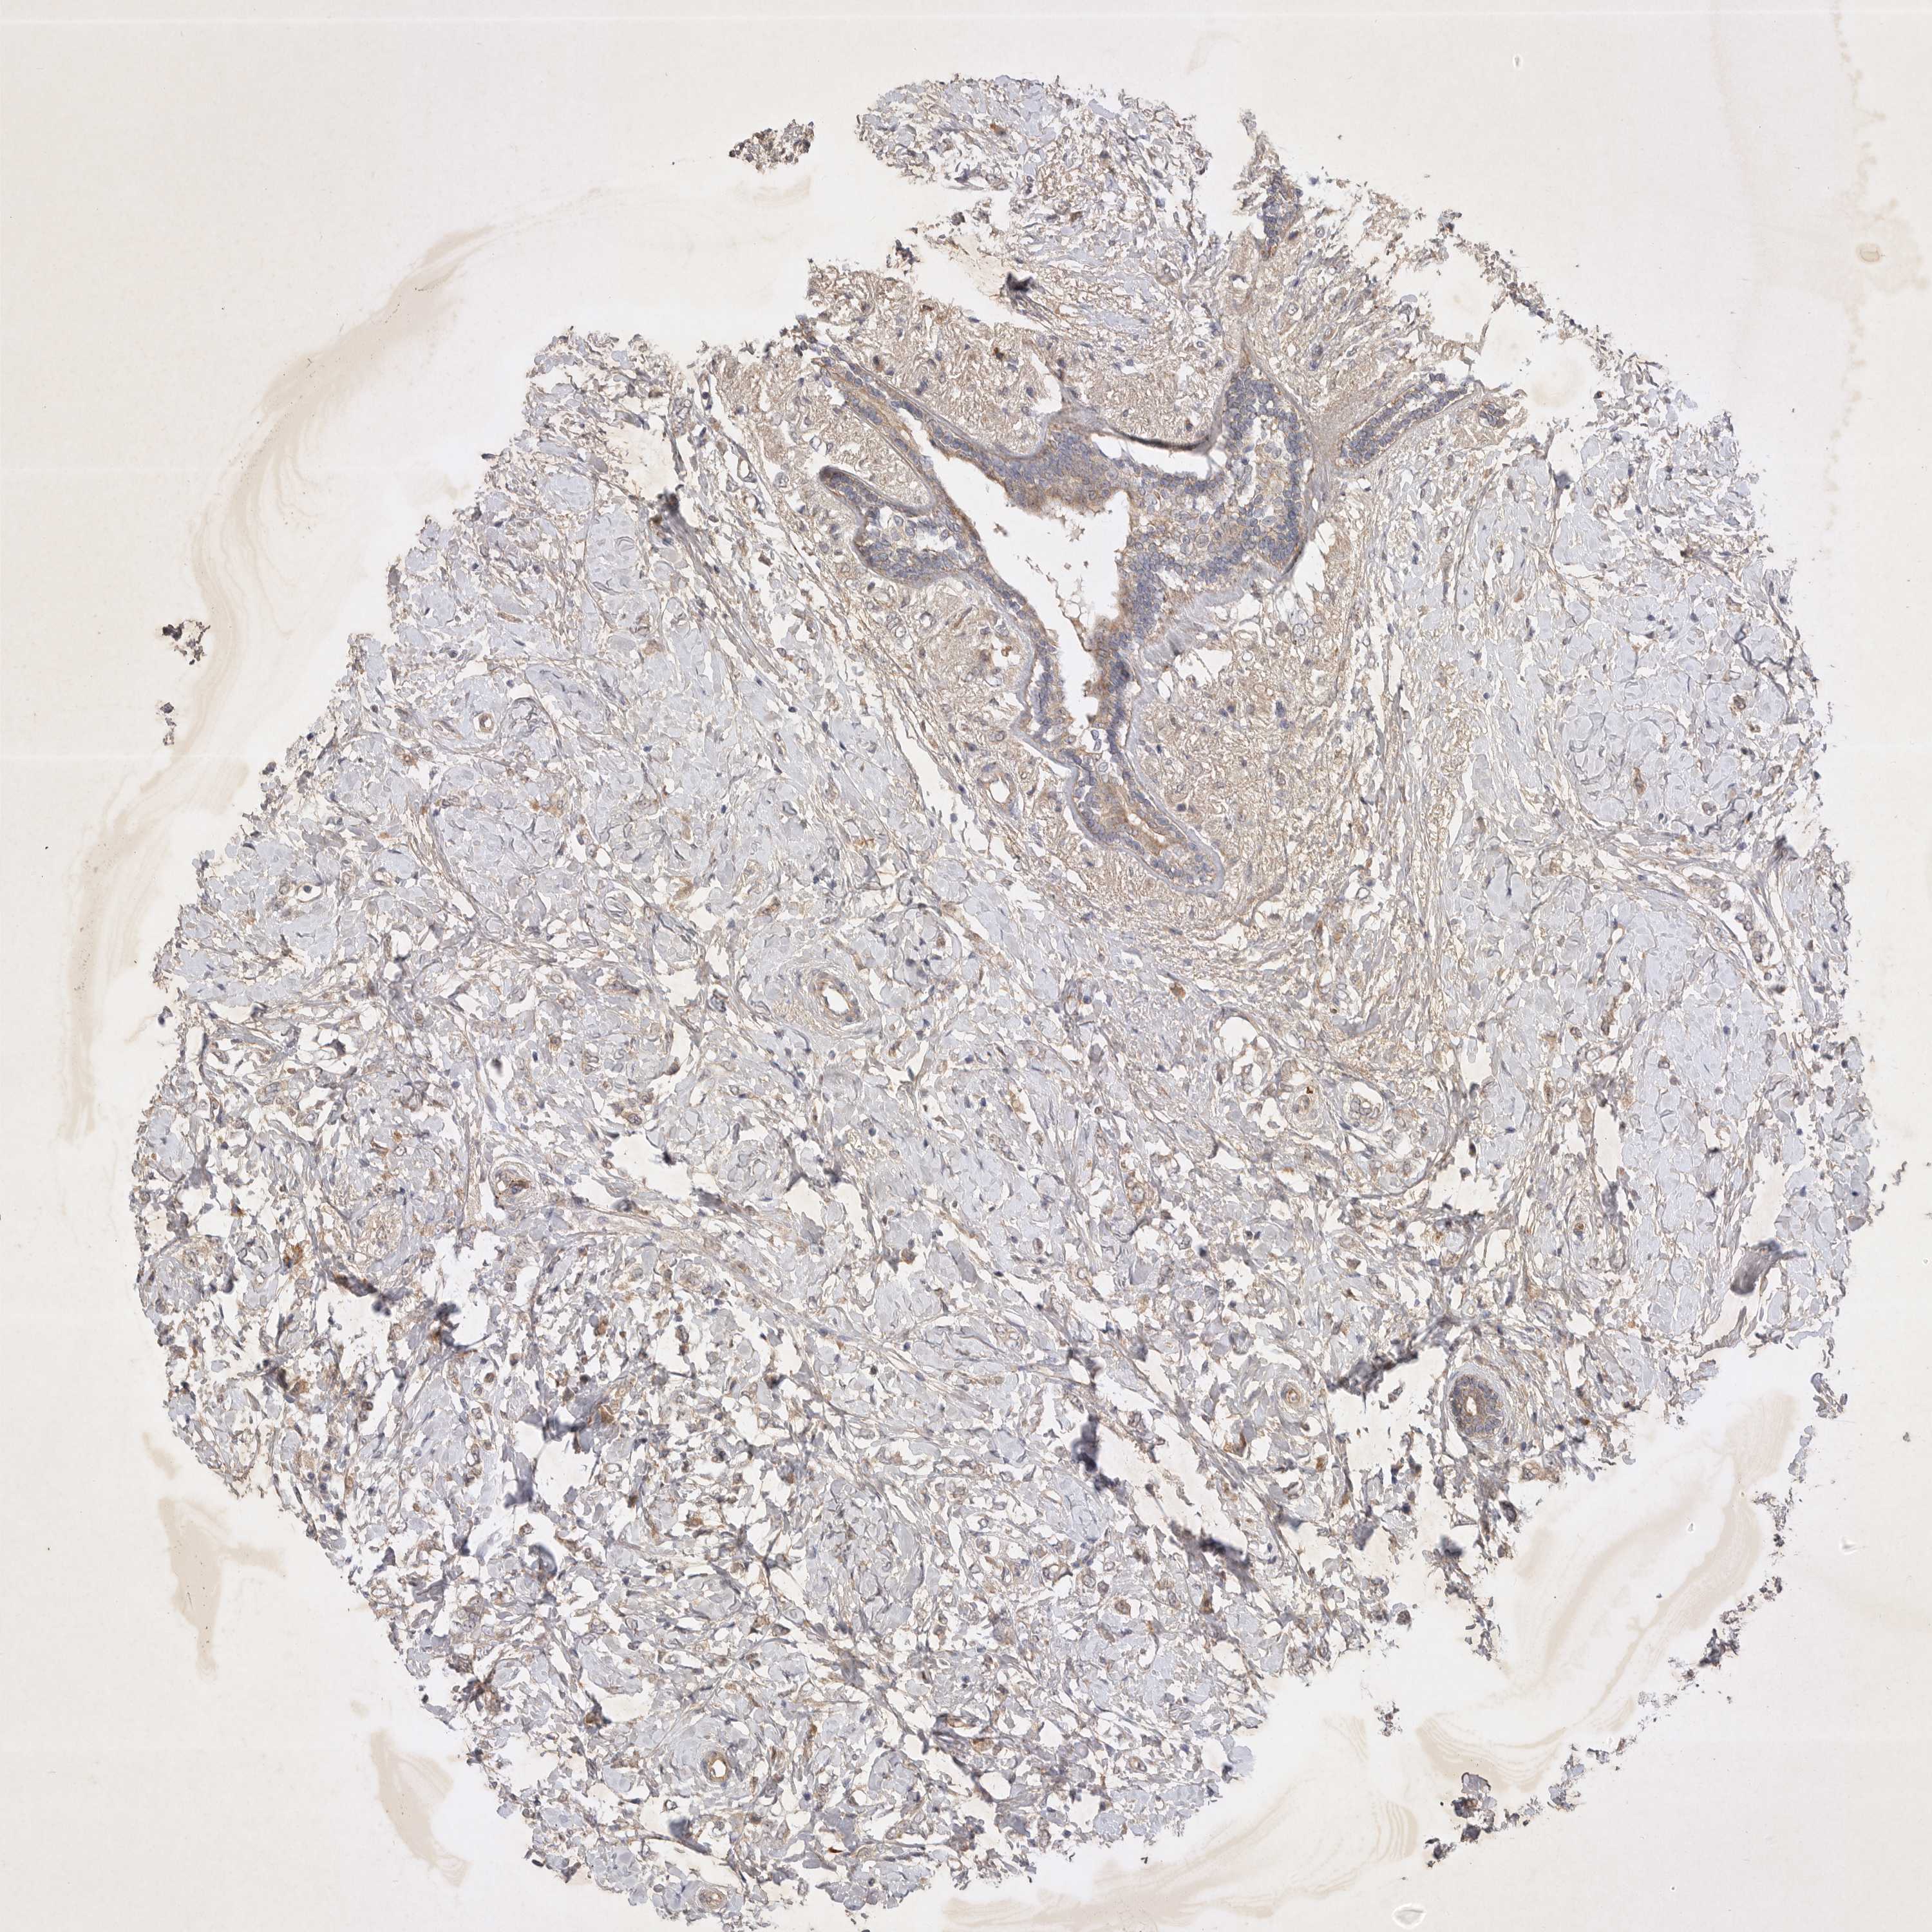

CANCER BREAST CANCER Show tissue menu

BRCA TCGA BRCA VALIDATION PROTEIN EXPRESSION

Breast cancer

Human cancer

Breast invasive carcinoma

PTPDC1 is not prognostic in Breast Invasive Carcinoma (TCGA)